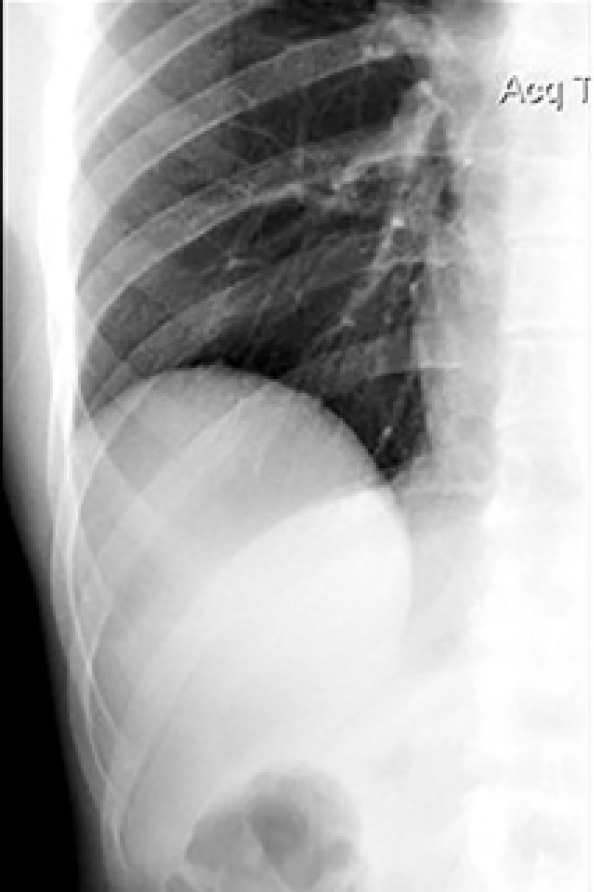

По данным предварительного просмотра полученных рентгенологических изображений возникла необходимость в выполнении прицельной рентгенографии области правого плеврального синуса для более углубленного обследования (рис. 3).

Рис 3. Прицельная рентгенография области правого плеврального синуса пациента Н. в положении стоя